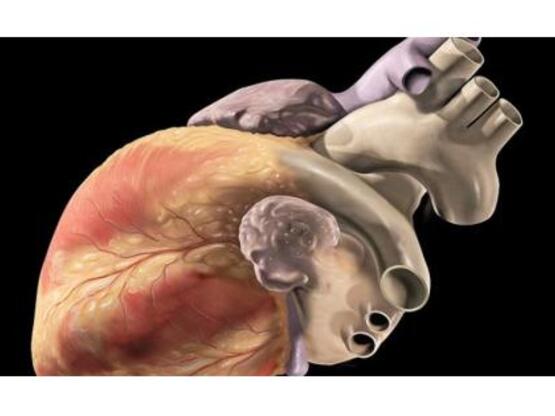

Βρετανοί επιστήμονες ανέπτυξαν μια νέα πολλά υποσχόμενη διαγνωστική τεχνική για την καρδιά, καλύτερη από τις υπάρχουσες έως τώρα, καθώς μπορεί να αμέσως να «δει» σε ποιο βαθμό είναι φραγμένες οι αρτηρίες ενός ανθρώπου και, συνεπώς, κατά πόσο αυτός κινδυνεύει από έμφραγμα. Είναι η πρώτη μη επεμβατική τεχνική, η οποία μπορεί να εντοπίσει τις πλάκες που είναι πιθανό να αποκολληθούν, σχηματίζοντας έτσι επικίνδυνο για την καρδιά θρόμβο.

Η νέα μέθοδος (τομογραφία εκπομπής ποζιτρονίων ή ΡΕΤ-CT), που έως τώρα χρησιμοποιείτο για την ανίχνευση όγκων σε καρκινοπαθείς, πρέπει να δοκιμαστεί σε μεγαλύτερο δείγμα καρδιοπαθών, προτού εισαχθεί στην κλινική πρακτική. Είναι η πρώτη φορά που καθίσταται δυνατό να εντοπίζονται με τόση ακρίβεια οι «ζώνες κινδύνου» του καρδιαγγειακού συστήματος, όμως η περαιτέρω έρευνα θα δείξει αν η έγκαιρη ανίχνευση των πλακών που μπορεί να οδηγήσουν σε θρόμβωση, στην πράξη είναι όντως σε θέση να σώσει τη ζωή πολλών ανθρώπων.

Η τεχνική χρησιμοποιεί αφενός μια ραδιενεργή ουσία, η οποία «φωτίζει» τις τυχόν επικίνδυνες πλάκες που φράζουν τη ροή του αίματος προς την καρδιά, και αφετέρου πολύ υψηλής ανάλυσης εικόνες που απεικονίζουν την καρδιά και τα αγγεία. Έτσι, ο γιατρός μπορεί να έχει στα χέρια του μια λεπτομερή εικόνα των επικίνδυνων ζωνών της καρδιάς.